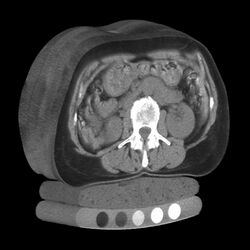

Image of cortical and trabecular bone of the spine by Quantitative computed tomography. Only the central trabecular portion is measured

At the spine, QCT is used to measure the bone mineral density of only the spongy interior bone separately from the dense cortical bone that forms the exterior walls of the vertebrae.[4] The trabecular bone has much higher metabolic activity than the cortical bone and so is affected by age, disease and therapy-related changes earlier and to a greater degree than cortical bone. This means that QCT of the spine has an advantage compared to other bone density tests because earlier changes in bone mineral density may be detected .[1]